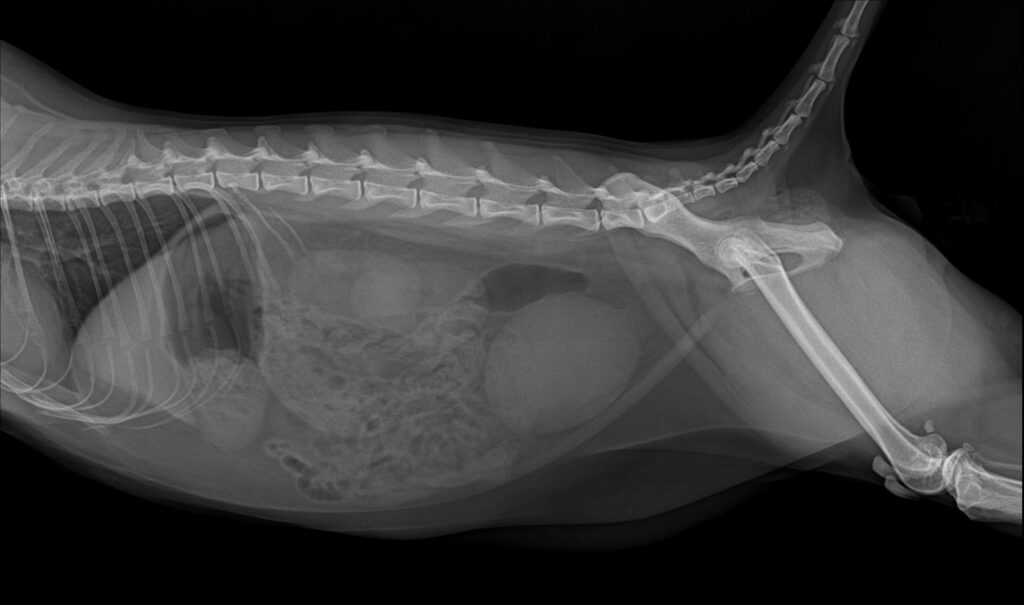

내원 후 환자는 복부 방사선 검사와 복부 초음파 검사를 진행했습니다. 복부 방사선 검사에서는 방광이 정상 범위를 넘어 심하게 팽대된 소견이 확인되었습니다.

환자의 복부 방사선 검사 / 출처: 미래동물의료센터